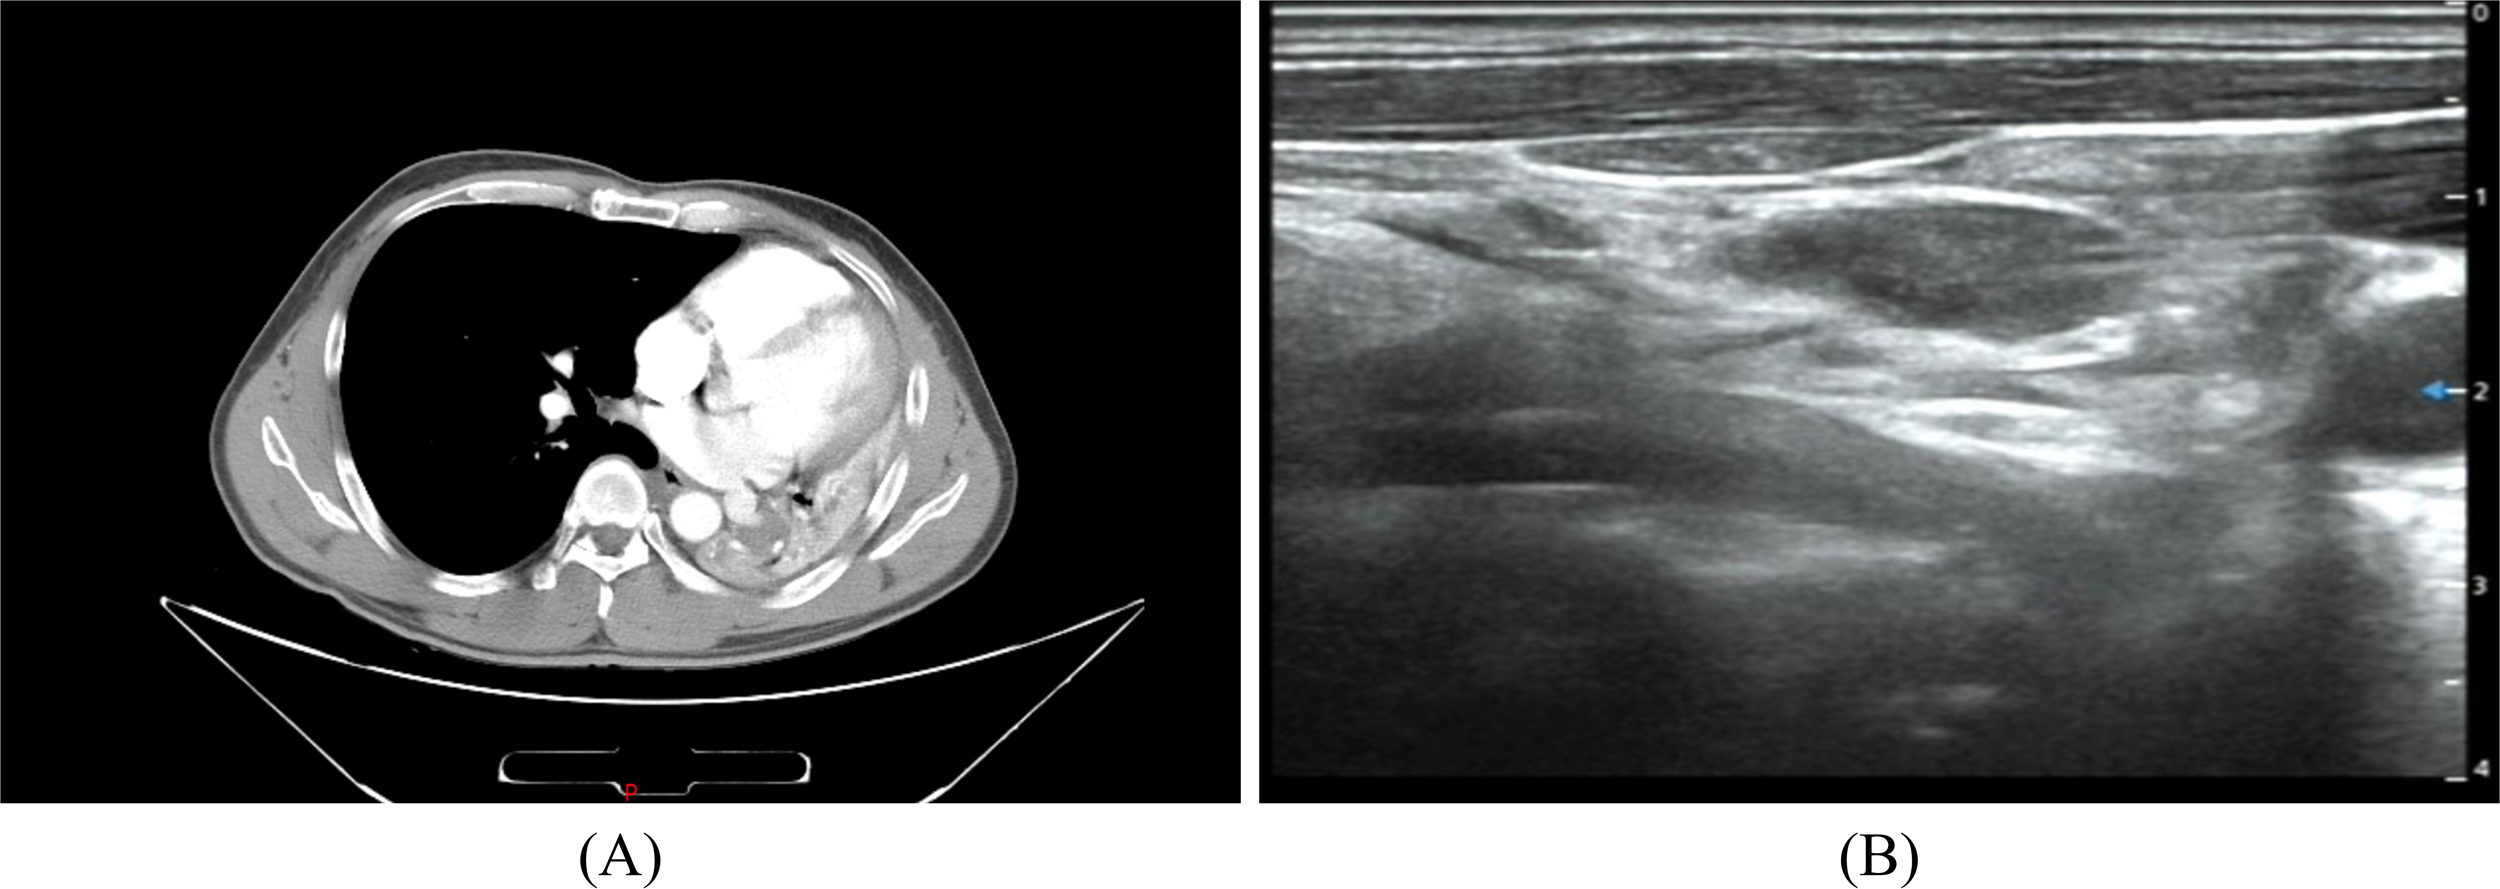

A 45-year-old male was admitted to the hospital for recurrence of MEC of the left lower lung more than one month after his last treatment. The patient initially visited the hospital in June 2021 because of chest and back pain, with a chest CT scan revealing several slightly weak and enhanced nodules in the left lower lobe, the largest being 2.2 cm × 1.4 cm, presenting as an irregular solid shadow (Figure 3A). A tracheoscopic biopsy revealed a poorly differentiated tumor. He subsequently underwent a left lower lobectomy with bronchial sleeve resection and mediastinal lymph node dissection. Intraoperative freezing showed negative bronchial margins and lymph nodes. Postoperative pathology confirmed MEC invading the cartilage. Histopathological examination with hematoxylin and eosin (HE) staining revealed a mixture of squamous cells, intermediate cells, and mucinous cells. The glandular structure containing mucin is obvious, with moderate nuclear pleomorphism and some hyperchromic nuclei (Figures 4A-C). Immunohistochemistry was positive for Ki-67 (+, 10%), CK5/6(+), CK7(+), P63(+), and p40(+) (Figures 4D-F), consistent with MEC. The patient was diagnosed postoperatively with stage IIB (pT3N0M0) disease and received four cycles of chemotherapy with docetaxel and cisplatin from August to November 2021.

Figure 3

www.frontiersin.org

Figure 3. Chest CT (A) The left lung is reduced in volume and multiple nodules are seen in the lower left lung. Neck ultrasound (B) Multiple swollen lymph nodes in the neck.